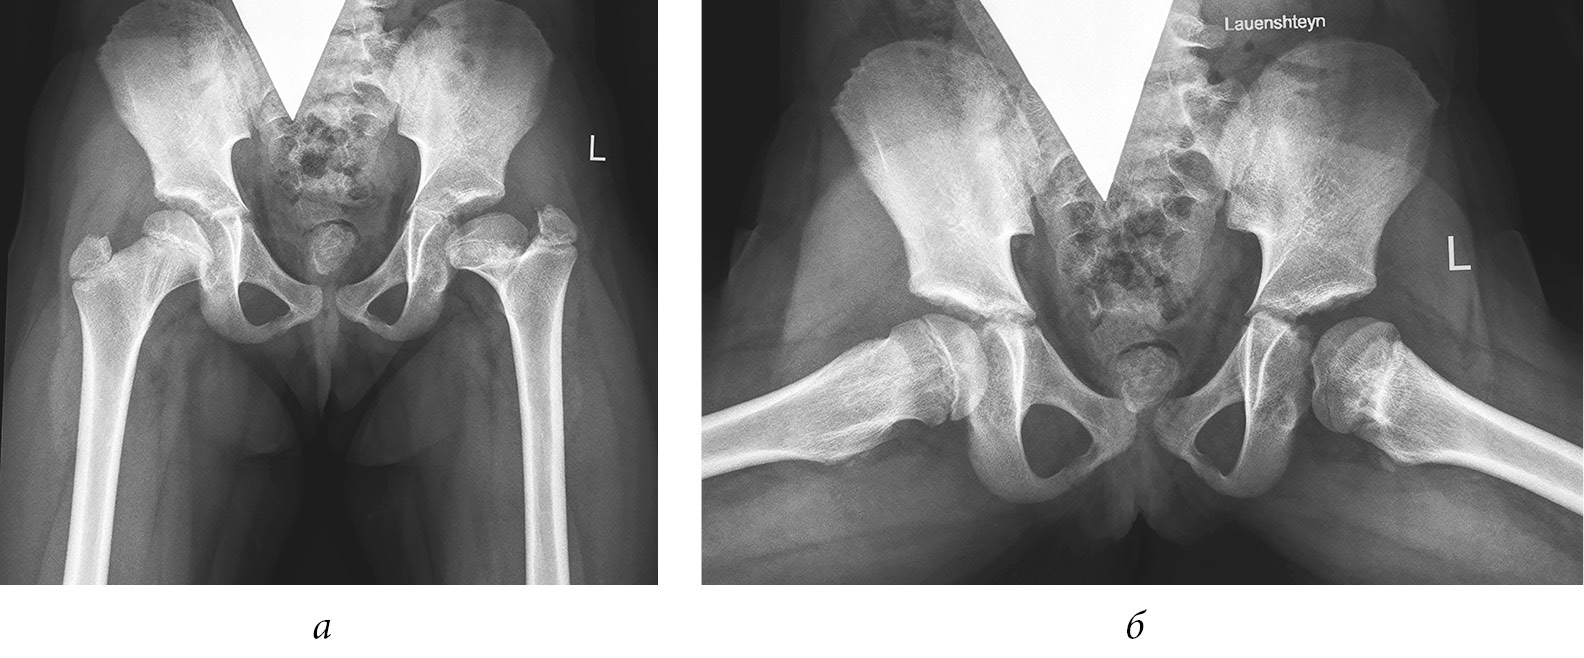

Рис. 3. Рентгенограммы пациентки Ш. Формирование многоплоскостной деформации проксимального отдела бедренной кости с высоким положением большого вертела после перенесенного аваскулярного некроза головки бедренной кости (справа — IV типа, слева — II типа по Kalamchi и MacEwen). В анамнезе — консервативное лечение по поводу врожденного вывиха бедра с двух сторон: а — в возрасте 1 года 2 месяцев; б — в возрасте 3 лет 9 месяцев; в — в возрасте 11 лет

2) последствия гематогенного остеомиелита (септического артрита) — 101 (28,9 %) ребенок. В эту группу также вошли пациенты, перенесшие внутриутробные инфекции и хирургические вмешательства на первом году жизни по поводу врожденных пороков сердца, атрезии пищевода, кишечной непроходимости, трахеопищеводных свищей, осложнившиеся инфекционным поражением тазобедренных суставов (рис. 4);

Рис. 4. Рентгенограммы пациентки Ж., 7 лет. Последствия гематогенного остеомиелита — многоплоскостная деформация проксимального отдела бедренной кости с высоким положением большого вертела слева: а — прямая проекция; б — проекция по Лауэнштейну